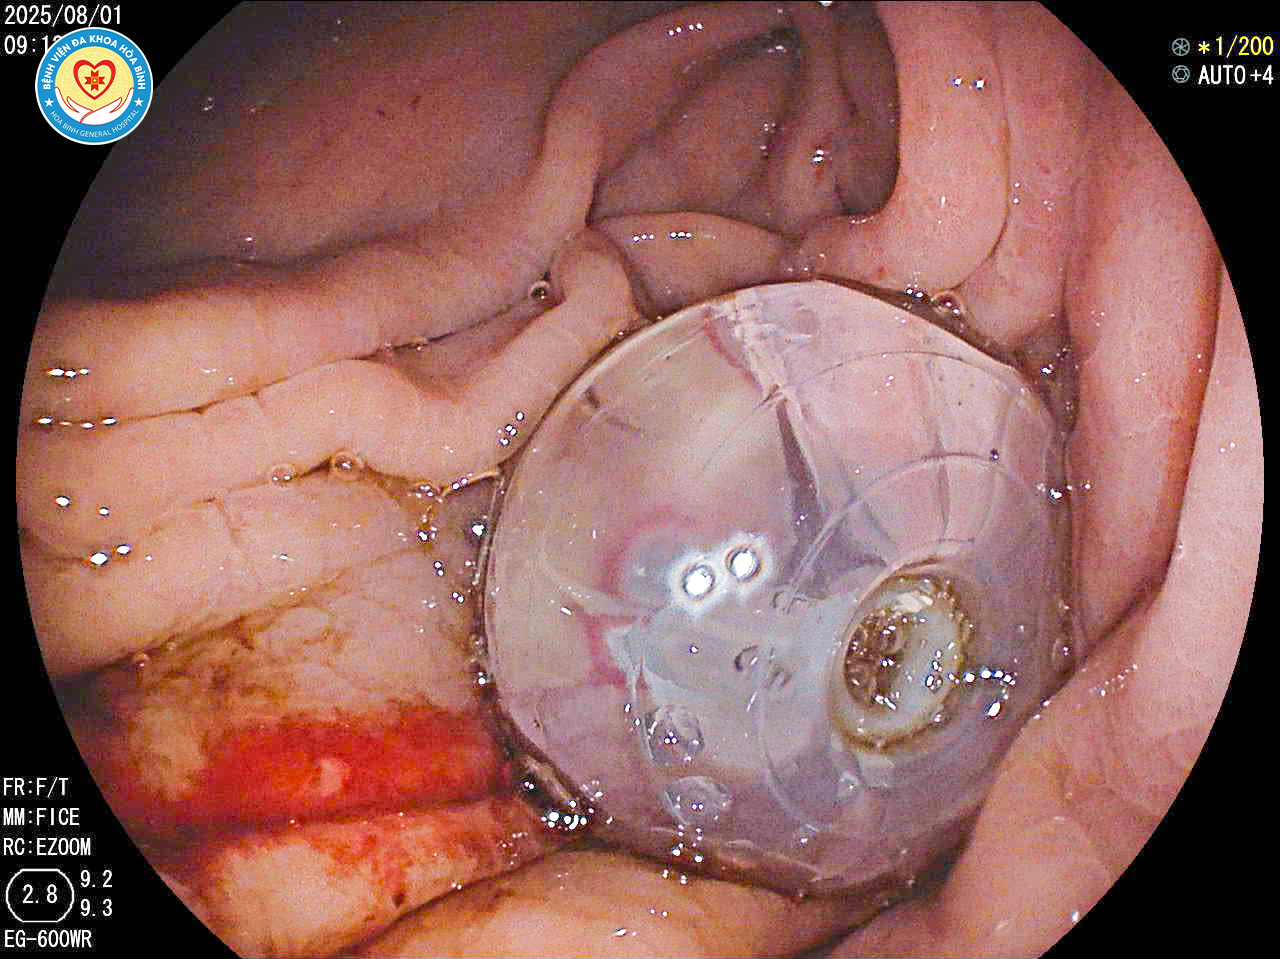

Hình ảnh các y, bác sĩ thực hiện kỹ thuật mở thông dạ dày qua nội soi

Nhằm nâng cao chất lượng điều trị và chăm sóc bệnh nhân, Bệnh viện Đa khoa Hòa Bình đã triển khai thành công kỹ thuật mở thông dạ dày qua nội soi (PEG – Percutaneous Endoscopic Gastrostomy), đánh dấu một bước tiến quan trọng trong ứng dụng kỹ thuật nội soi can thiệp hiện đại tại tỉnh.

Theo đại diện Khoa Nội tiêu hoá, thủ thuật được thực hiện nhanh chóng, an toàn, ít xâm lấn và mang lại hiệu quả điều trị cao. Sau khi đặt ống, bệnh nhân có thể bắt đầu nuôi ăn qua sonde trong vòng 6 - 24 giờ, giúp phục hồi thể trạng nhanh hơn đáng kể.